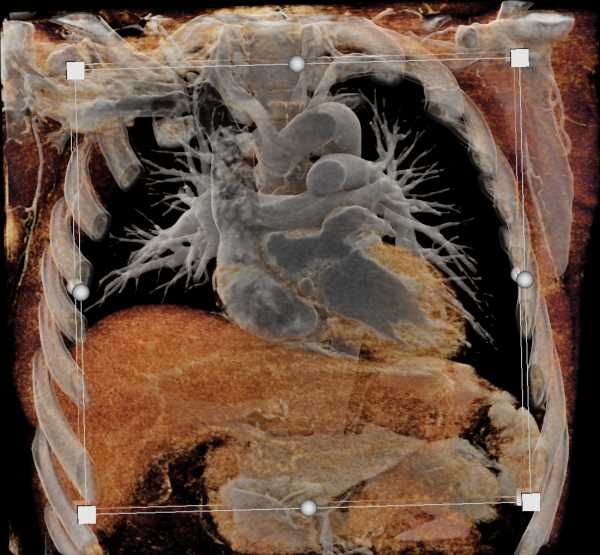

Aortic Valve Repair